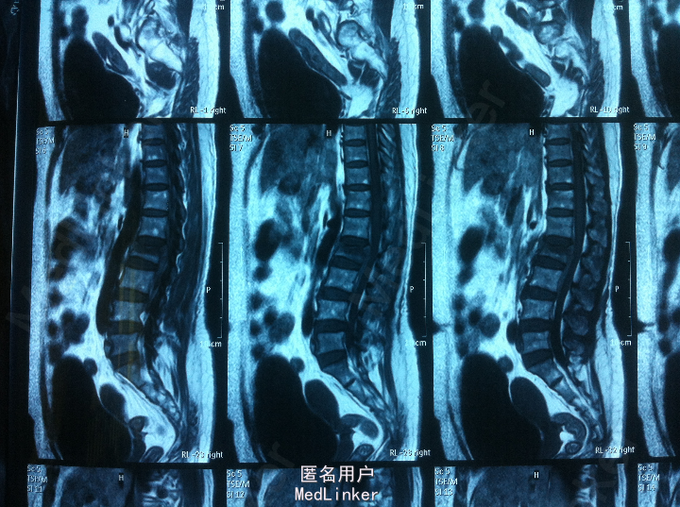

高处摔伤腰部疼痛、活动受限1入院。 中年女性,既往健康; 患者1天前从3米高处摔伤,臀部着地,及感腰部疼痛、活动受限,双下肢无放射性疼痛、麻木,双下肢活动可。

PE:腰部轻度后凸,叩痛,双下肢感觉无减退,双下肢肌力4-5级,巴氏征 阴性。 X-ray:腰2椎体骨折 CT:腰2椎体骨折,椎体后缘不连续 MR:腰2椎体骨折,腰2-3椎体水平硬膜外血肿

诊断:腰椎骨折 腰椎硬膜外血肿 处理:腰椎后路撑开复位内固定